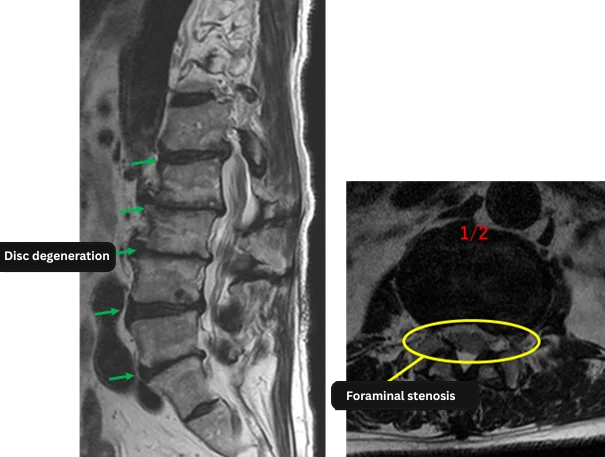

L1/2: degeneration, left disc herniation, left foraminal stenosis, endplate degeneration

L2/3: degeneration, disc bulging, decreased disc height, right foraminal stenosis, endplate degeneration

L3/4: degeneration, disc bulging, decreased disc height, right foraminal stenosis, endplate degeneration

L4/5: degeneration, left disc herniation, left foraminal stenosis, endplate degeneration

L5/S: degeneration, disc bulging, left foraminal stenosis, endplate degeneration

The above findings were also observed on the imaging.

Disc degeneration, disc herniation, foraminal stenosis, and endplate degeneration were observed across all five levels (L1/2, L2/3, L3/4, L4/5, and L5/S), which were highly likely to be the cause of the patient’s primary symptoms.